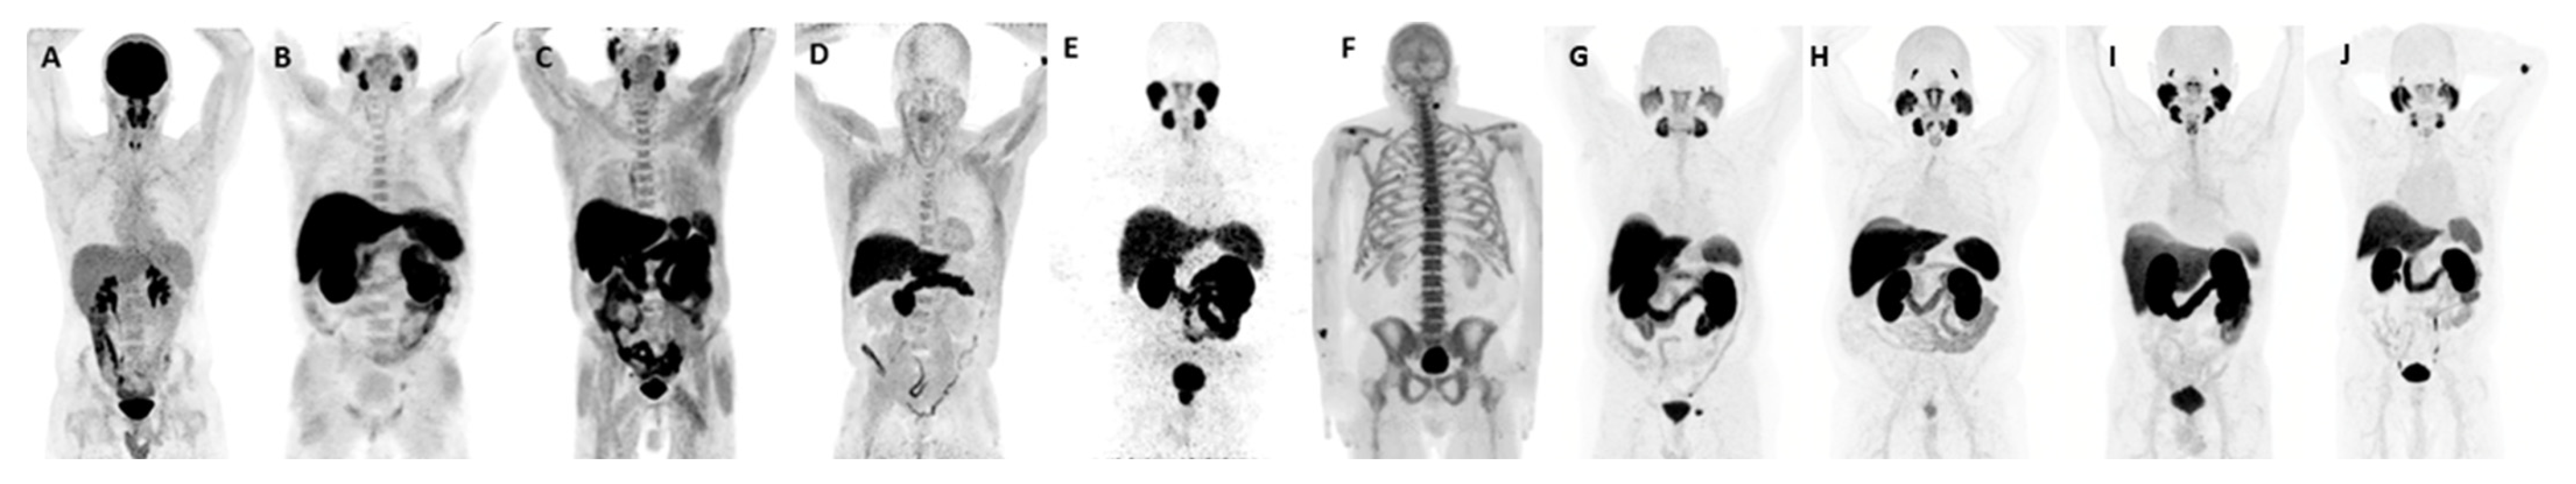

- Hofman, M.S.; Hicks, R.J.; Maurer, T.; Eiber, M. Prostate-specific Membrane Antigen PET: Clinical Utility in Prostate Cancer, Normal Patterns, Pearls, and Pitfalls. Radiographics 2018, 38, 200–217. [Google Scholar] [CrossRef]